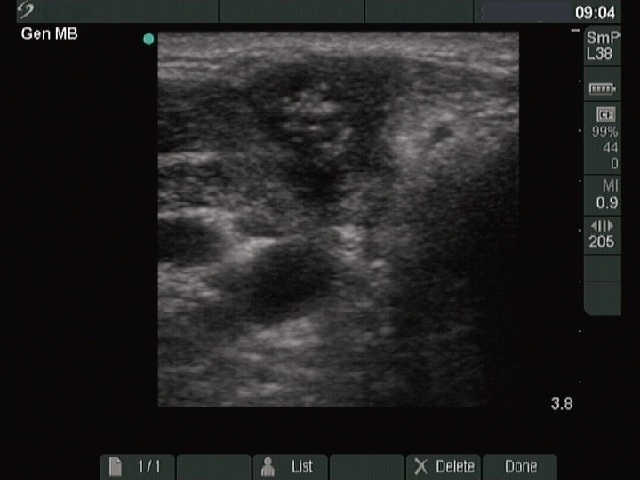

Granulation around surgical thread (histological diagnosis) - case 1386

This is a typical presentation of a granulation around surgical thread: a hypoechogenic, irregularly shaped, avascular mass having several echonormal areas corresponding to a ragged tissue.